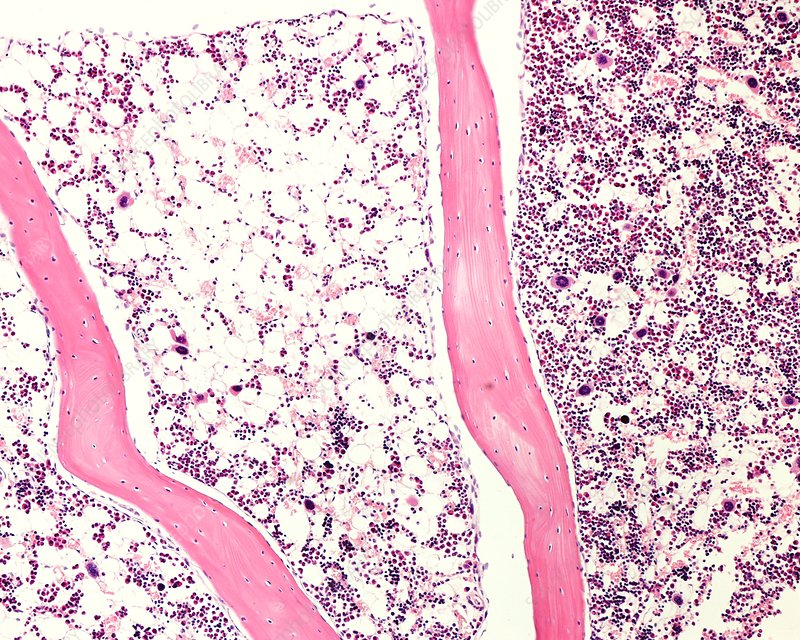

<p>Identify the marrow to the left.</p>

Identify the marrow to the left.

yellow